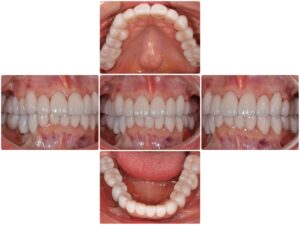

術後の患者様の感想

むし歯をずっと放置していて、歯も茶色くなってしまい、もうずっと歯を見せて笑うことはしていなかったのですが、全て綺麗な白いセラミックにしていただいてからは、どの角度から見られても自信をもって笑うことができます。

本当に人生が変わった治療です。ありがとうございます。

治療費 |

インプラント52万円/1本 セラミック21万円/1本 矯正治療125万円~ 歯周治療25万円 (全て税別) |

リスク |

リテーナー不使用による矯正治療の後戻り 治療終了後のメンテナンス不足による歯周病 歯ぎしりや過剰な噛み締めによるセラミックの破損 |